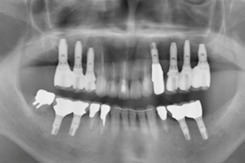

全顎インプラント治療

治療前

治療後